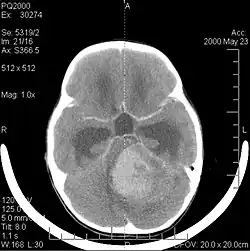

Computertomografie (CT) en magnetische resonantiebeeldvorming (MRI) kunnen neoplasie in de hersenen effectief detecteren. MRI is gevoeliger dan CT voor het identificeren van laesies, maar heeft contra-indicaties voor patiënten met pacemakers, incompatibele prothesen, metalen clips en andere. CT blijft de voorkeursmethode om calcificaties in laesies of boterosie van het kalotje of de basis te detecteren. Het gebruik van contrastmiddelen, die gejodeerd zijn in het geval van CT en paramagnetisch (gadolinium) in het geval van MRI, maakt het verkrijgen van informatie over de vascularisatie en integriteit van de bloed-hersenbarrière mogelijk, een betere definitie van de tumorachtige tumor vergeleken tot het omringende oedeem en het genereren van hypothesen over de mate van maligniteit. Het radiologisch onderzoek maakt ook een beoordeling mogelijk van de mechanische effecten en de daaruit voortvloeiende veranderingen in hersenstructuren als gevolg van de tumor, zoals hydrocefalus en hernia's, waarvan de effecten fataal kunnen zijn. Ten slotte kan deze diagnostiek, ter voorbereiding op een operatie, worden gebruikt om de locatie van de laesie of de infiltratie van de tumor in vitale delen van de hersenen te bepalen. Voor dit doel is MRI efficiënter dan CT omdat het driedimensionale beelden kan opleveren. Diagnostische radiologische beeldvormingshulpmiddelen benadrukken de verandering in neoplastisch weefsel in vergelijking met normaal hersenparenchym (door veranderingen in elektronisch afgebeelde weefseldichtheid op CT en signaalintensiteit op MRI). Zoals de meeste pathologische weefsels zijn tumoren ook herkenbaar aan een verhoogde ophoping van intracellulair water. In het computertomogram lijken ze hypodens, dwz met een lagere dichtheid dan het hersenparenchym, in het kernmagnetische resonantietomogram met spin-roosterrelaxatie hypointenseen in spin-spin ontspanning evenals proton weging (PD) hyperintens.

Computertomografie van de hersenen toont typisch een weefselmassa die door beide contrasten kan worden versterkt. Op CT lijken laaggradige gliomen gewoonlijk isodense aan het normale parenchym en vertonen daarom mogelijk geen contrastversterking. Evenzo zijn laesies in de achterste schedelgroeve moeilijk te identificeren op CT. Bijgevolg zijn de resultaten van een dergelijke tomografie alleen niet altijd voldoende voor diagnostische doeleinden. In twijfelgevallen is het gebruik van de meer gevoelige magnetische resonantiebeeldvorming essentieel.

Aan -MRI toont een intracraniële tumor als een massieve laesie die na gebruik van het contrastmiddel meer luminescent kan worden. Er is echter altijd een signaalafwijking in -Magnetic resonance imaging, die de aanwezigheid van neoplasie of vasogeen oedeem aangeeft. Gewoonlijk is verhoogde luminescentie (contrastversterking) indicatief voor een tumor met een hogere graad van maligniteit. Kenmerkend voor glioblastoom is een contrastring, waarbij het lichtgevende deel overeenkomt met het vitale deel van de kwaadaardige tumor en het donkerdere -hypointens gebied dat overeenkomt met weefselnecrose.